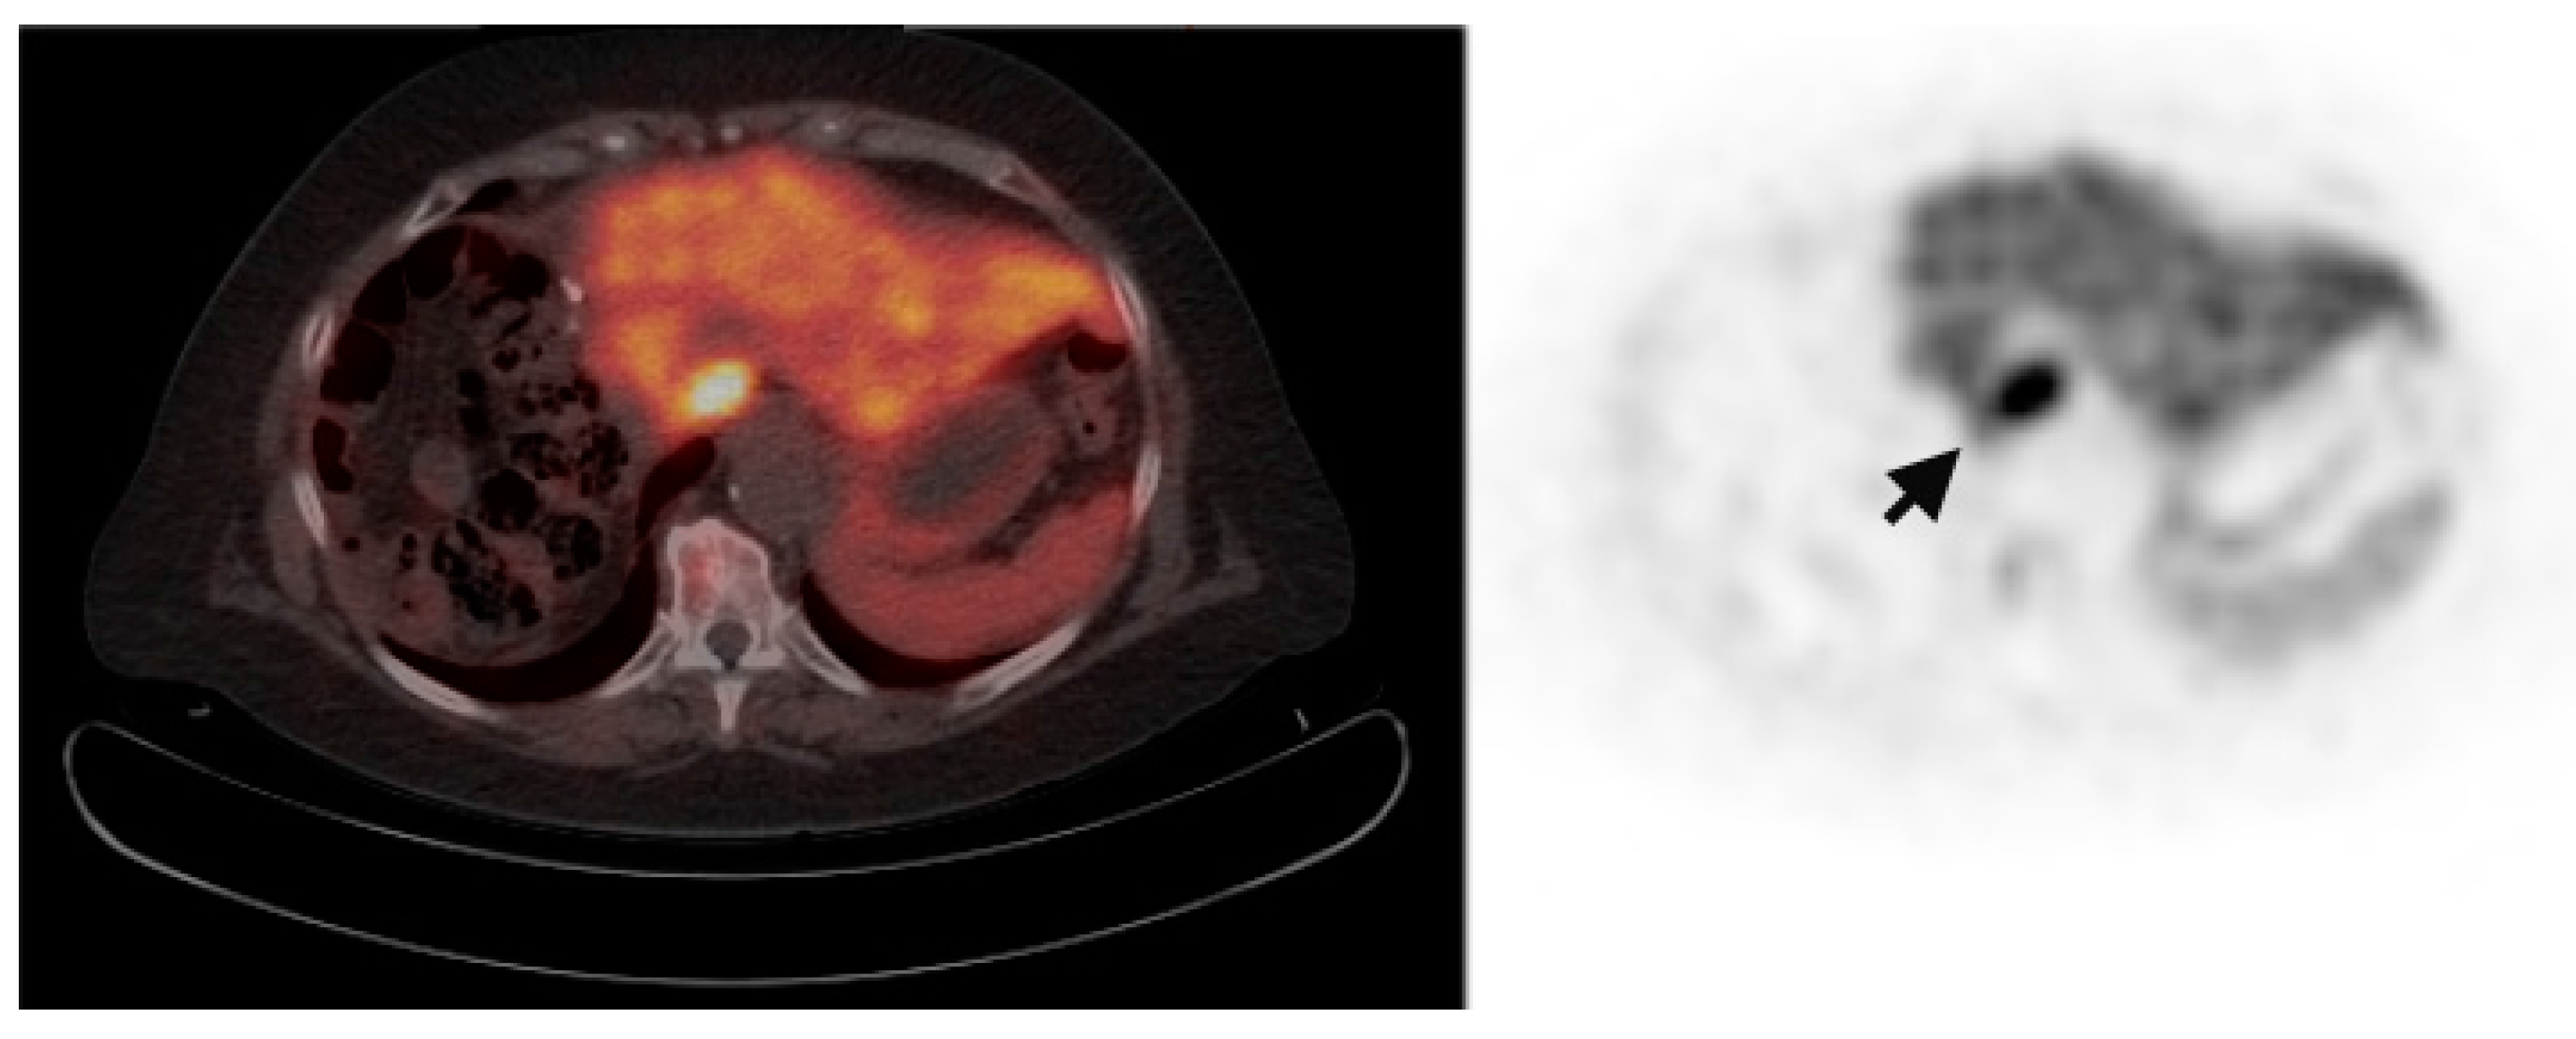

Multiple foci of increased FCh uptake in the liver consistent with multifocal or multinodular HCC (example, Figure 1) were noted in 8 of the 13 patients with increased primary tumor uptake. Of these, the areas of increased FCh uptake were adjacent to the treatment site (examples, Figure 2 and Figure 3) in 2 patients treated by local tumor ablation and 1 patient treated by liver resection. In one newly diagnosed case, PET demonstrated heterogeneous tumor FCh uptake with increased peripheral uptake and markedly diminished central uptake (Figure 4). Pathology in this case revealed a highly-necrotic tumor with Edmondson-Steiner grade 3 differentiation.

Figure 4.

Metabolic heterogeneity in HCC. Corresponding PET/CT (left) and PET (right) shows a heterogeneous region of increased uptake within the liver in this patient with newly diagnosed liver mass. Two small satellite tumors (arrows) are adjacent to the dominant mass (arrowheads surround). Histologically, this was a poorly differentiated HCC tumor.